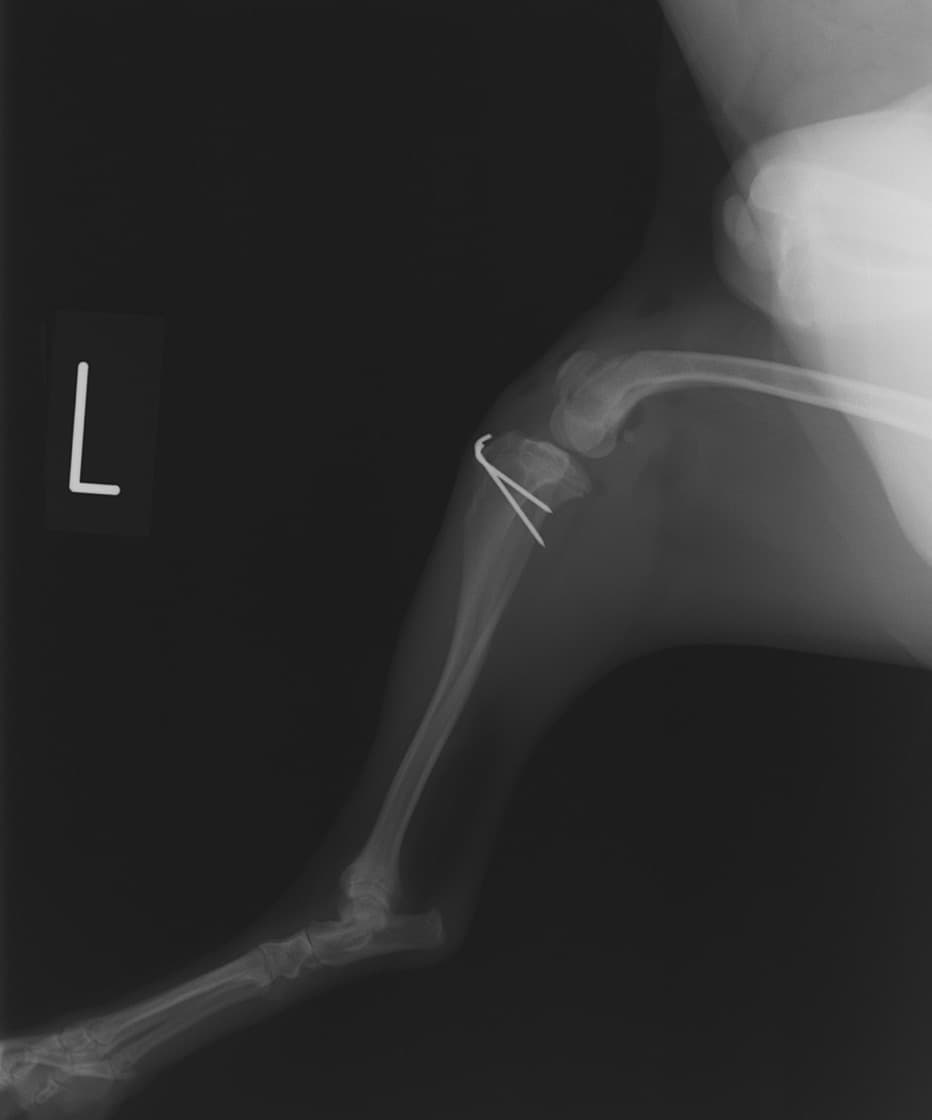

■ 症例24 キャバリア 7か月

左右膝蓋骨内方脱臼(左:グレードⅣ 右:グレードⅢ)

以前から左右後肢の跛行が認められ、整形外科学的検査・レントゲン検査により左右の膝蓋骨脱臼が認められた。症状が重度である左膝の膝蓋骨脱臼整復術を行った。外科手技は縫工筋及び内側広筋の解放、脛骨粗面の外側転位、滑車ブロック形造溝術、内外側関節方の縫縮を実施した。術後一か月時点で、左の膝蓋骨は安定しており経過は良好である。

本症例は成長期における重度の膝蓋骨脱臼であり、術後の再発の可能性もあるため、経過をしっかりと観察していく必要がある。また、今回手術を実施していない右膝に関しても経過を観察し、手術を検討していくこととする。